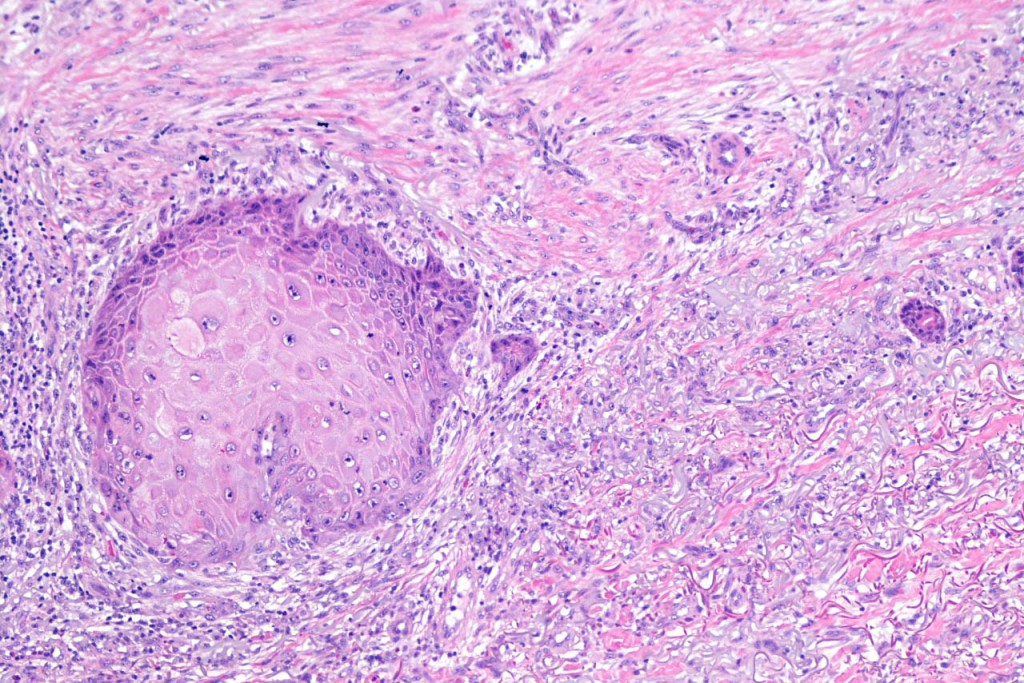

•Well differentiated squamous epithelium often with a characteristic ground-glass appearance

•Only mild pleomorphism & basally located mitoses

Below is a fascinating case shared on McKee Derm by Dr. James Simpson. There is an obvious keratoacanthoma but at the edge of the lesion there is marked atypia with nuclear enlargement and pleomorphism. This is also evident in the adjacent epidermis and in the deeper nests.